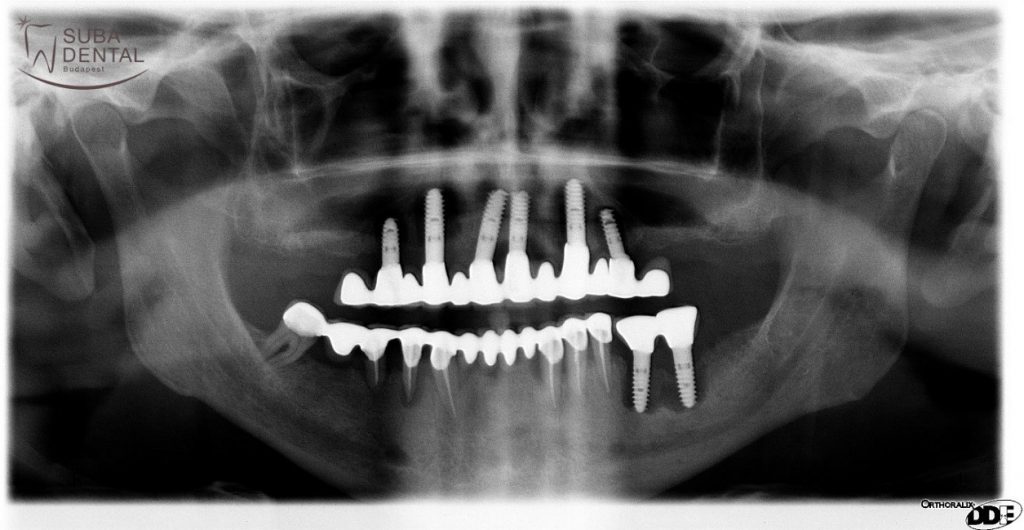

Panoramic radiography was performed and intraoral X-ray scans were recorded of the current condition in order to determine the cause of the problem. It was readily visible in the X-rays recorded that both the patient’s teeth and the implants previously received were beyond repair and the inflammation, infection, bone resorption and peri-implantitis around them indicated the removal thereof (explant surgery). These dental foci may, among other things, cause heart disease, hair loss, dermatological issues and joint complaints.

Due to the omission of regular check-ups and heavy smoking all the implants had to be removed as they had all developed peri-implantitis around them. Bridge replacement was out of the question. The dark shadow around the implants signifies peri-implantitis.